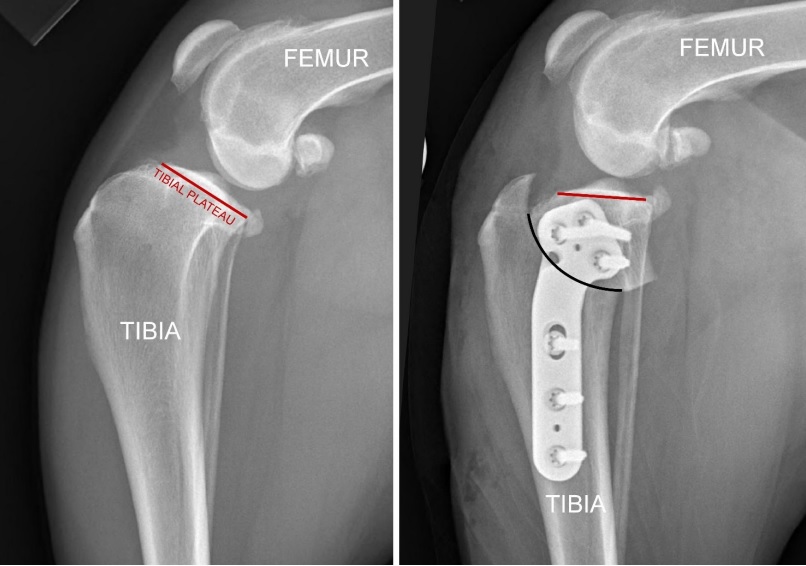

Radiographs (X-rays) provide additional information that can be helpful. It allows the veterinarian to see effusion (fluid) in the knee and bone spurs (osteophytes) around the knee, both of which indicate there is a problem in the knee. In some cases, one can also see that the femur (thigh bone) has slid backward on top of the tibia (shin bone), which does indicate CCL rupture. However, in cases of “partial rupture” there are times when both the physical exam and the radiographs are subtly abnormal. Since the CCL cannot be seen on an X-ray, the diagnosis is considered presumptive, or tentative, at this point.

WHAT IS TIBIAL PLATEAU LEVELING OSTEOTOMY

The TPLO is a procedure in which the tibia (shin bone) is cut, re-oriented, and stabilized to provide improved stability to the knee. Basic information can be found on this procedure here: https://kck9ortho.com/acl-tplo-shawnee-ks/